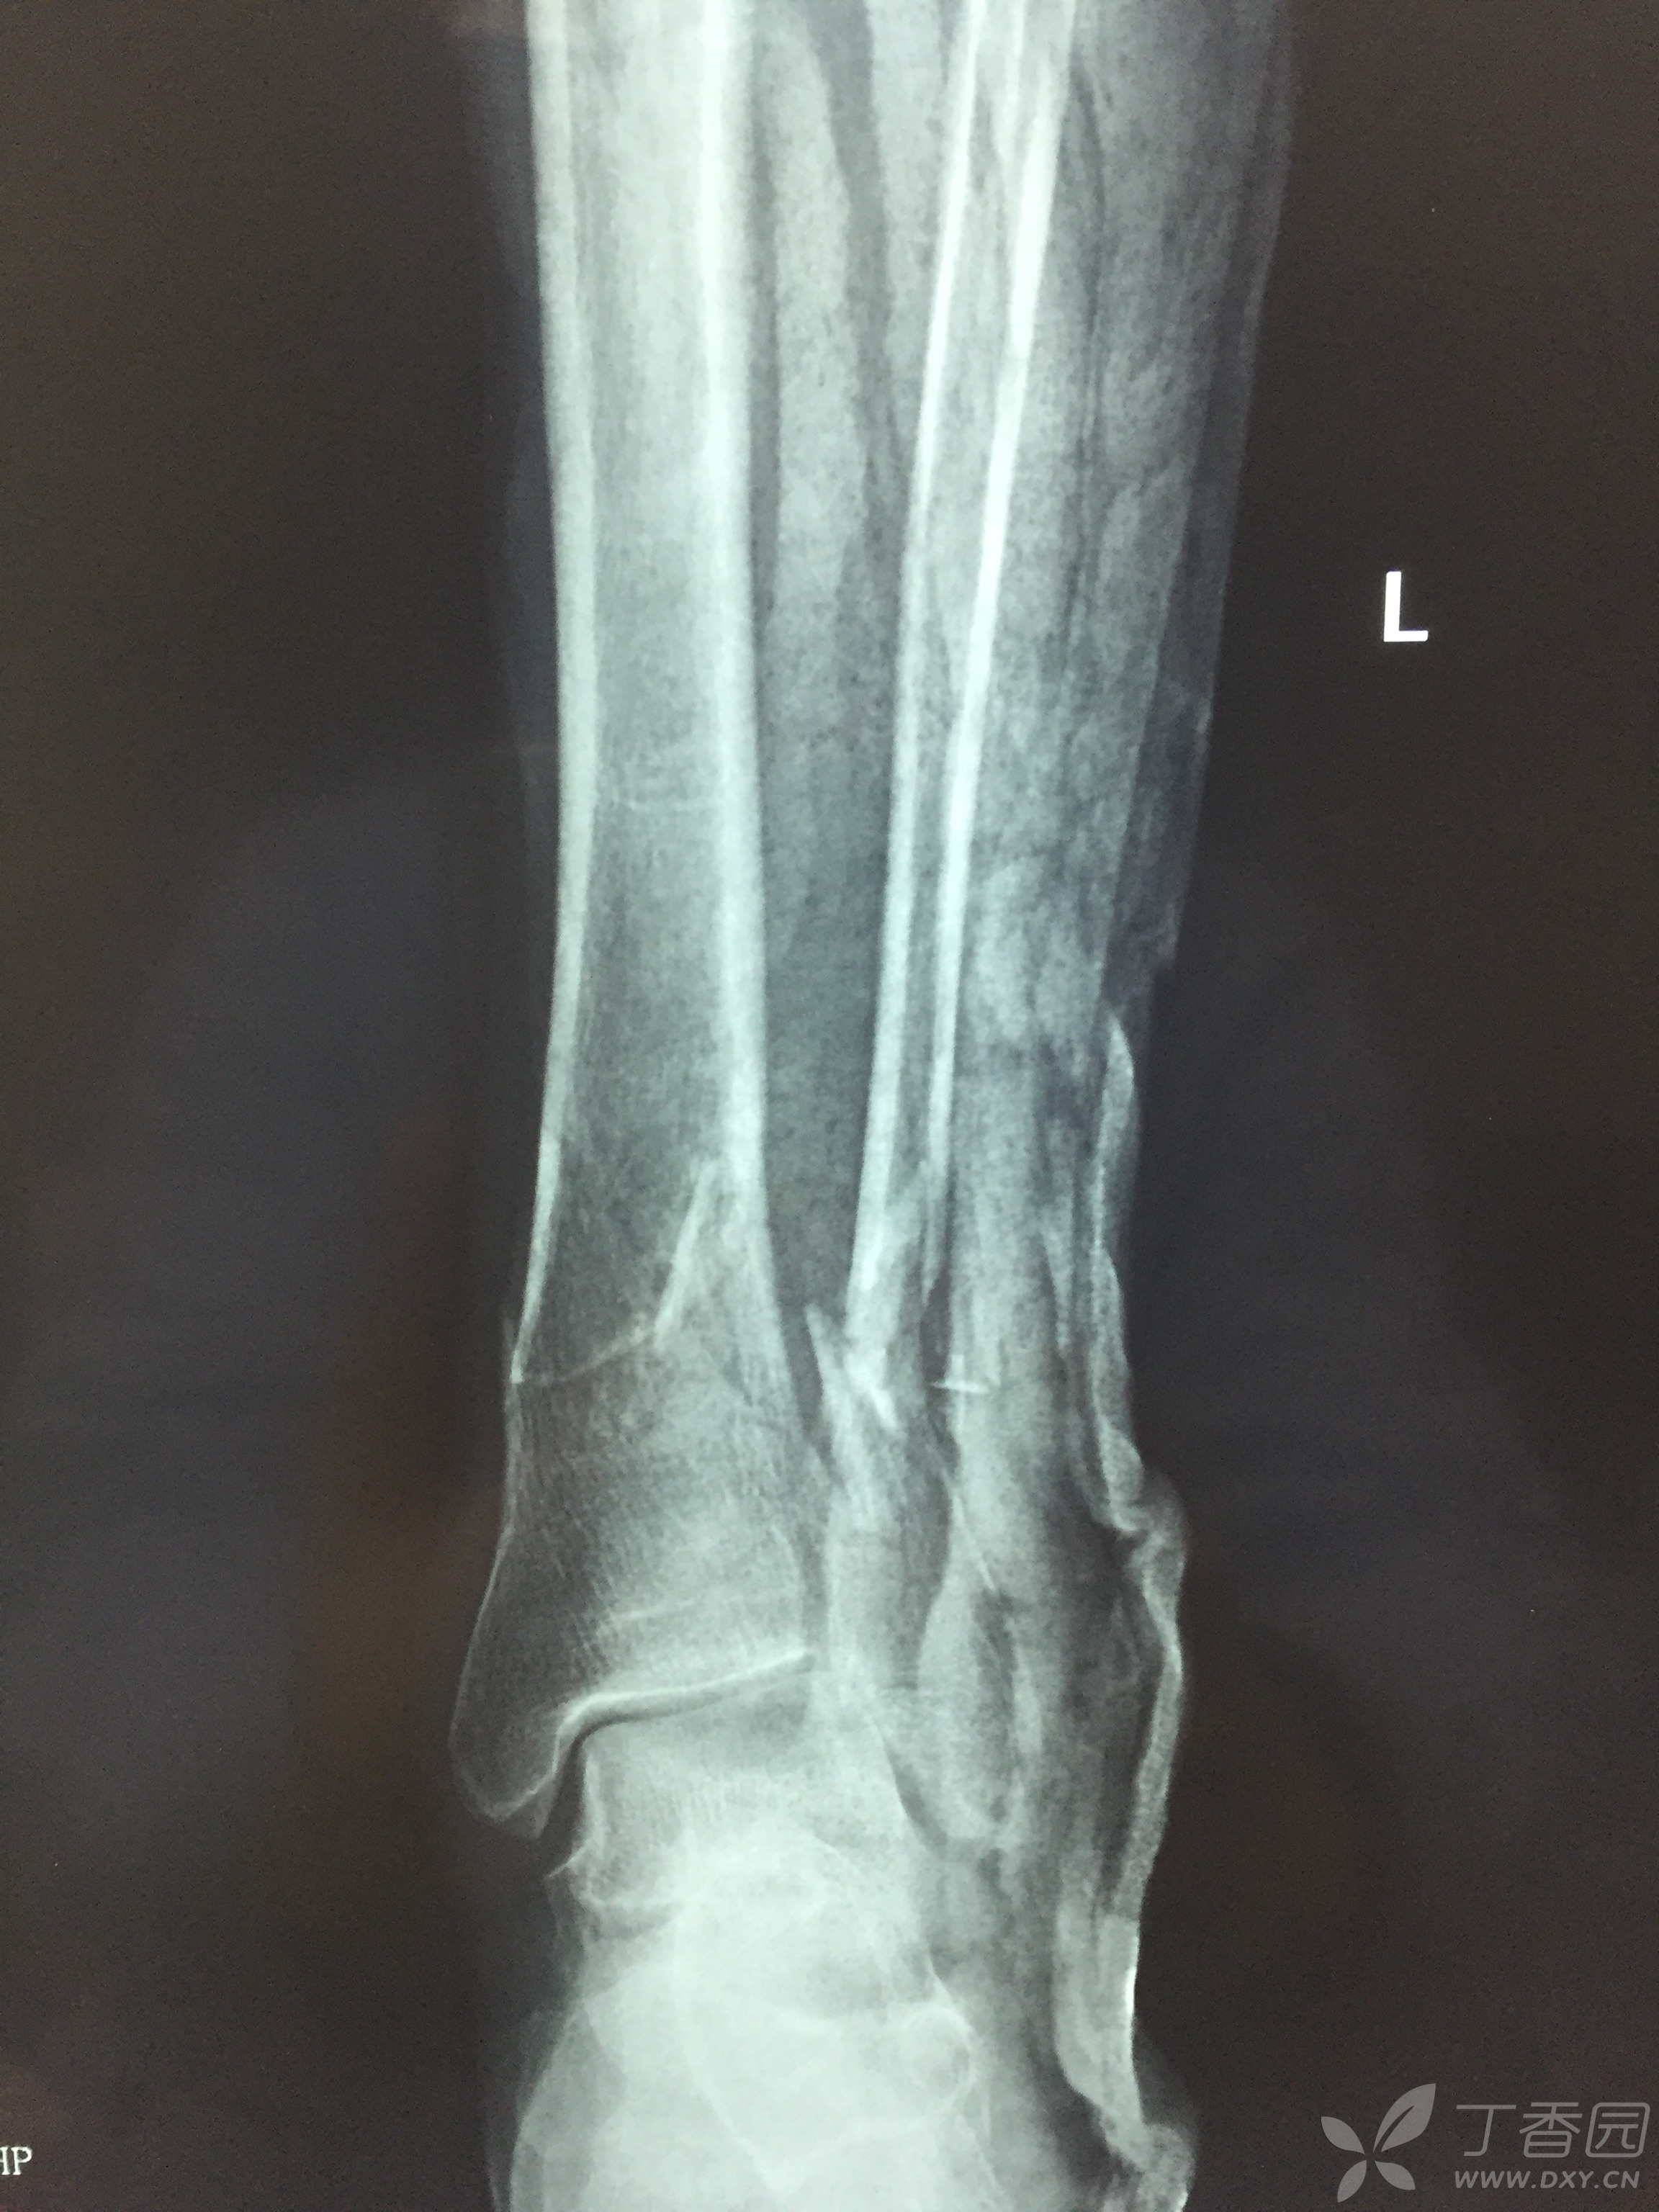

胫腓骨骨折 骨科专业讨论版 丁香园论坛

胫腓骨粉碎性骨折 骨科专业讨论版 丁香园论坛

黄骨头踝关节手术日记 开放性粉碎性pilon骨折合并腓骨下段粉碎性骨折一例 骨科专业讨论版 丁香园论坛